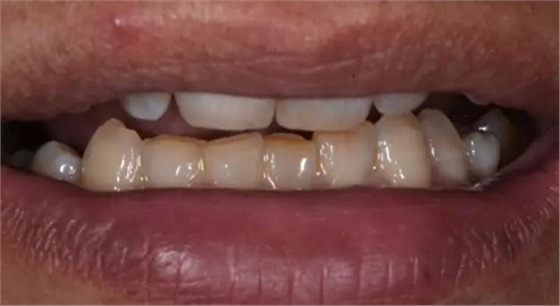

病例2:T女士,42歲。左上后牙缺失3年。就診要求恢復(fù)咀嚼功能。

X片上可見T女士左上后牙缺失。根據(jù)患者口內(nèi)和全身狀況。制定計劃為:右上后牙種植修復(fù)。

術(shù)后口內(nèi)照片

修復(fù)體戴入口內(nèi)后照片,與鄰牙鄰接良好。